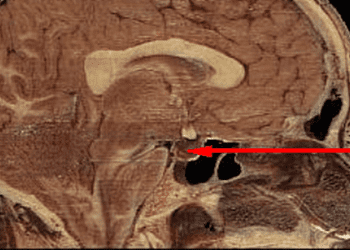

1. In this retrospective cohort study, two-thirds of incidental pituitary microadenomas remained unchanged or decreased in size over a median ...